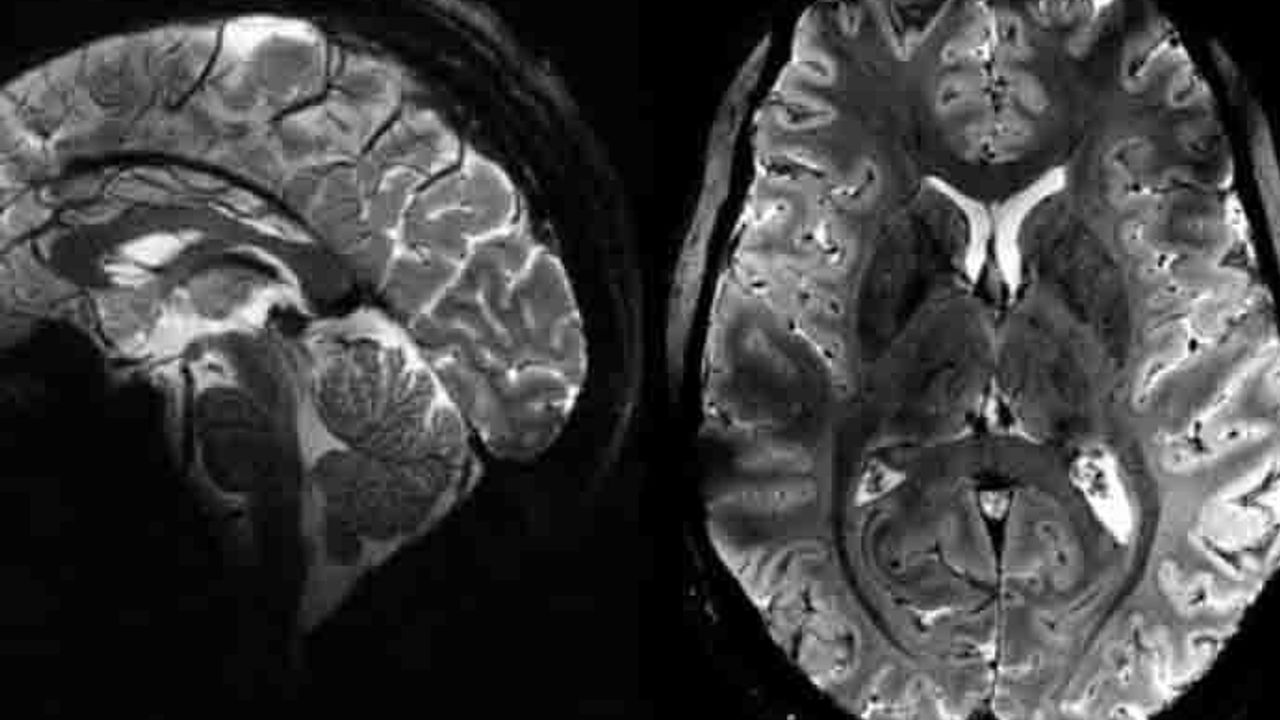

Dünyanın en güçlü manyetik rezonans görüntüleme (MRI) cihazıyla elde edilen, insan beyninin en net görüntüsünü yayınladı.

Fransa Atom Enerjisi ve Alternatif Enerjiler Kurumu CEA'dan yapılan yazılı açıklamada "Iseult" adlı MRI cihazıyla çekilen beyin görüntüsünün 20 yıldan uzun süren bir çalışma sonucu elde edildiği belirtildi. Yapılan çalışmalar kapsamında MRI cihazının son birkaç ay içerisinde yaklaşık 20 sağlıklı gönüllü üzerinde test edildiği kaydedilen açıklamada, neredeyse 4 dakikada en net beyin görüntüsünün elde edildiği aktarıldı. Açıklamada, 11,7 Tesla manyetik güce sahip Iseult MRI makinesiyle kısa sürede çekilen görüntülerin, hastanelerde yaygın kullanılan cihazlarla elde edilmesinin saatler sürebileceği kaydedildi. Iseult Projesi Başkanı ve CEA Araştırma Direktörü Nicolas Boulant, yaptığı açıklamada, verilerin daha yüksek kalitede elde edilebilmesi için araştırmanın birkaç yıl daha devam edeceğini belirterek, hedeflerinin 2026-2030’a kadar nörodejeneratif hastalıkların yanı sıra şizofreni ve bipolar bozukluğu gibi psikiyatri alanındaki birçok hastalığı araştırmak olduğunu ifade etti. Iseult MRI cihazı ile elde edilen ultra detaylı anatomik bilgilerin, Alzaymır ve Parkinson gibi hastalıkların teşhisinde yardımcı olması bekleniyor. https://tele1.com.tr/insan-beyni-hakkinda-yeni-bulgular-bulundu-551281/